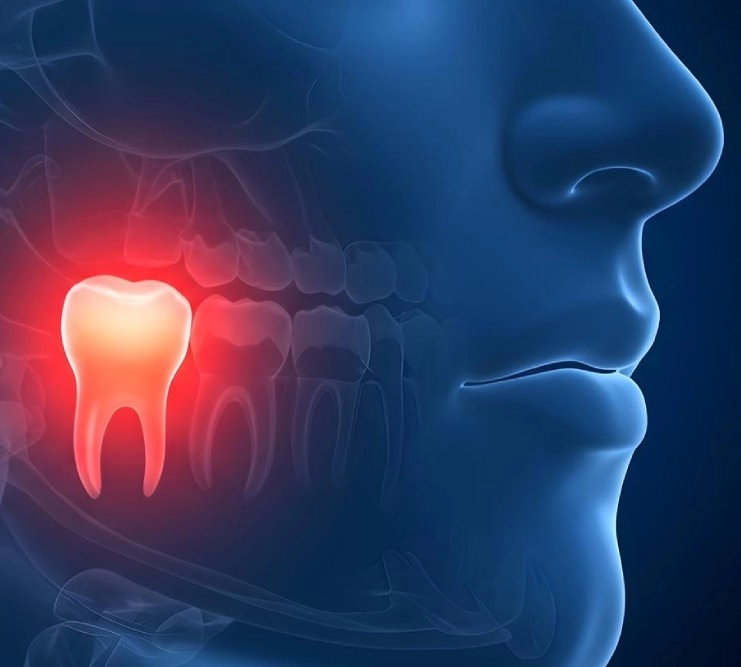

Зубы мудрости — самые дальние жевательные единицы, которые расположены настолько глубоко в полости рта, что даже не участвуют в самом процессе пережёвывания, либо участвуют — но недостаточно эффективно. Однако, своим расположением затрудняют гигиену и служат источником многих болезней.

Прорезывание восьмёрок приходится на возраст от 18 до 26 лет. К этому времени челюсть человека уже полностью сформирована, как и прикус. И дальнейшее прорезывание дополнительных зубных единиц затруднено тем фактом, что места для них (в большинстве случаев) уже не остаётся. Поэтому зубы мудрости одним своим появлением провоцируют множество проблем: смещение зубного ряда, воспаления, боль, образование десневого капюшона.

Из-за отсутствия места они растут неправильно и порой вообще не могут прорезаться. Такие "утопленные" в челюстной ткани зубы, мешающим им прорезаться, называются дистопированными. И наличие ретинированных/дистопированных зубов мудрости — прямое показание к хирургическому их удалению.